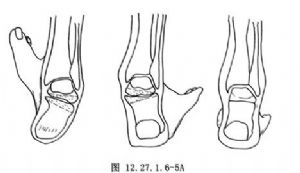

用大切骨刀切除跟骨和距骨关节面,根据畸形的性质与程度,切除适量的楔形骨质。如为内翻畸形,应切除以外侧为基底的楔形骨质;反之如为外翻畸形,则应切除以内侧为基底的楔形骨质(图12.27.1.6-5A)。用切骨刀横行切除跟骰关节面,如有足前部内收,应切除以外侧为基底的楔形骨质;如为外展畸形,则应切除以内侧为基底的楔形骨质(图12.27.1.6-5B)。切除距舟关节面,如有高足弓,应切除以背侧为基底的楔形骨质。如显露困难,宜在内侧做一纵行辅助切口。切骨后观察足部畸形矫正情况,适当修整骨面,使三处骨面有良好接触,以便完全矫正畸形,并有利于骨愈合(图12.27.1.6-5C)。保留取下的骨质,去除软骨部分,作为松质骨植骨,植于各关节周围,要特别注意在距舟关节部位多植些碎骨,防止形成假关节。